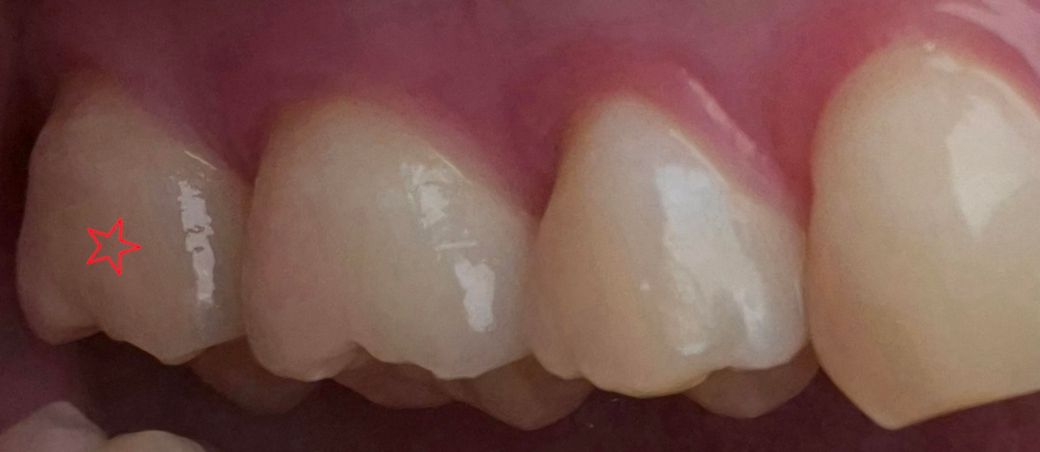

왼쪽 위에 있는 맨 끝쪽 어금니의 잇몸이 살짝 내려가보입니다 (별표 친 치아입니다)

3주전에 뿌리안쪽까지 스케일링할때도 안 아팠고, 음식 씹을 때도 안 아픕니다. 엄청 차가운거 먹어도 하나도 안 아프고 시리지도 않아요

그리고 치과에 가서 물어보니 이 정도 퇴축은 다들 있다고 하고.. 보통 이것보다 더 심한경우도 많아도 이식수술까진 안한다던데... 맨끝쪽 어금니가 원래 퇴축이 잘 온다고 하던데 맞을까요?

이정도는 정상범주로 보면 됩니다. 그리고 어금니는 잇몸 퇴축되어도 잇몸이식 거의 하지 않습니다. 앞니의 경우 미용 목적으로 합니다.

사진으로 보이는 부분은 양치질을 할 때 자극이 많이 되어 잇몸이 내려간 것으로 보입니다. 하지만 크게 문제되는 수준은 아닙니다. 자극이 지속되면 잇몸이 더 내려갈 수 있으니 잇몸에 가해지는 힘을 줄여주는 것이 좋습니다.